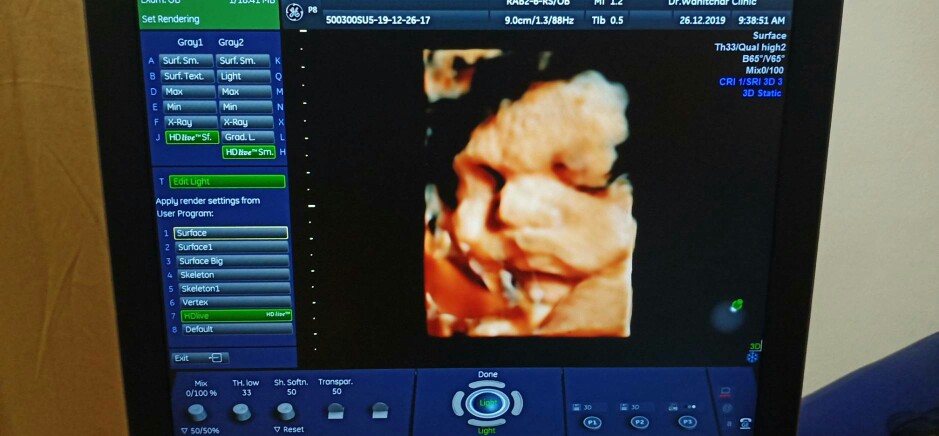

32wค่ะ

3D ตอน32w